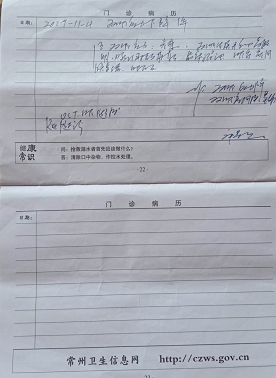

“因对工伤八级不服,经过多次调解,常州一建第二项目部与挂靠常州市钟楼区恒邦劳务公司老板都不愿调解。因我们当时没签劳动合同,老板没交工伤保险,工伤是我们自己报上去的,只是雇用工,希望有关部门领导能够帮帮我们。”在江苏省常州市新北区务工的陈新春女士致函有关部门反映说。

我把情况反应给省劳动鉴定委员会和工伤保险处有关工作人员。当时劳动鉴定委员会工作人员叫我鉴定时把出院后拍的片子给他们看,不看报告单,因报告单涉嫌隐瞒伤情骨折,况且省里把我住院的片子报告单都调过去了。最后我眼睛细网膜委缩电脑单子打不出来,到省跟劳动鉴定委员会工作人员讲,请他们公平公正鉴定,当时其答应我会公平公正鉴定的。2020年1月11日,在省级机关医院鉴定,我请他们公平公正鉴定,劳动鉴定委员会工作人员说,对鉴定结果不服可以司法鉴定。还有一个讲,只鉴定骨折,不鉴定器官和眼睛。我一个只有小学文化程度的普通妇女,也不知道这是不是符合有关规定。